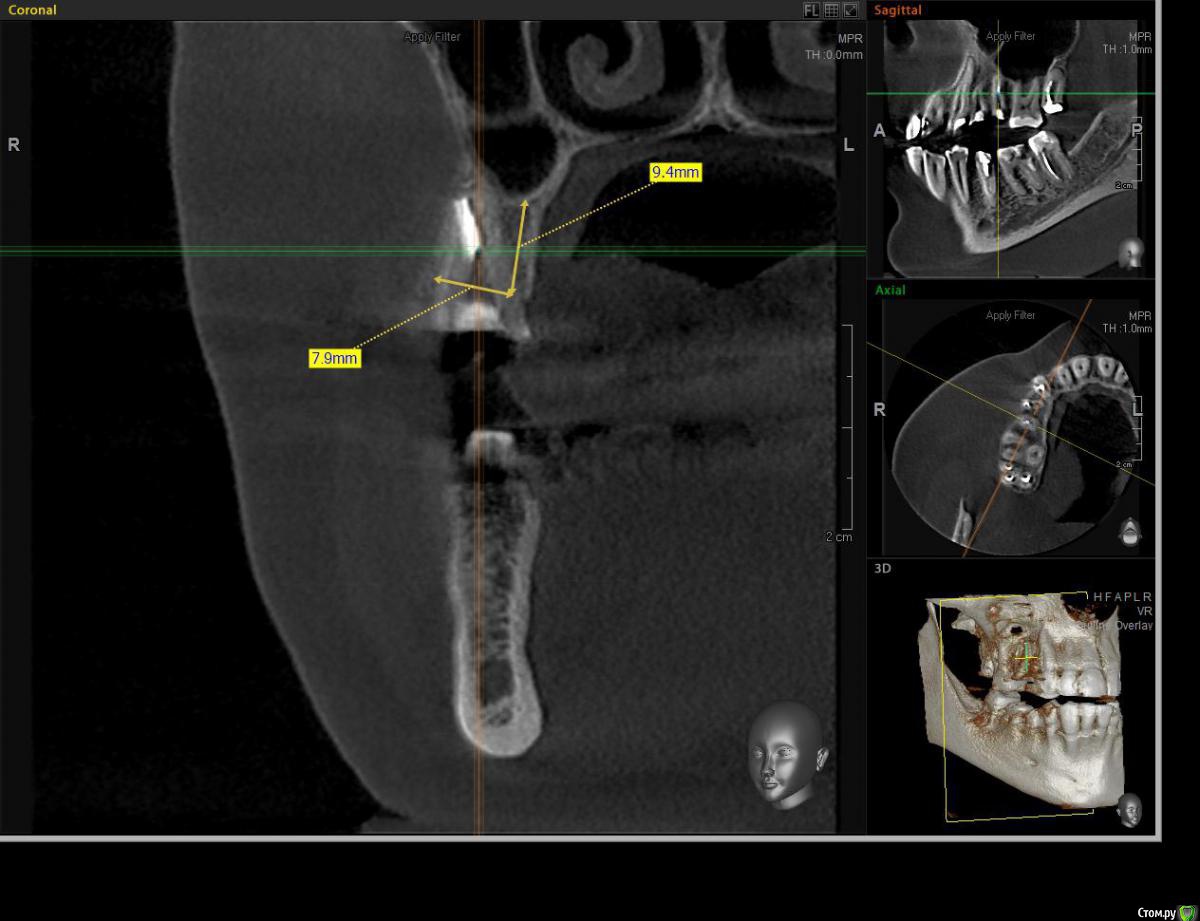

AlexanderGudkov Опубликовано 5 июля, 2017 Автор Поделиться Опубликовано 5 июля, 2017 Александр, формик 8.5 не нашёлся чтоль?))При этой позиции импланта для 8,5 пришлось бы море кости спилить))Так - то я широкие фдм люблю))http://s014.radikal.ru/i328/1707/ba/95cd7072120e.pnghttp://s019.radikal.ru/i603/1707/12/0f67ce0cd861.png Ссылка на комментарий

ossa-rr Опубликовано 22 августа, 2017 Поделиться Опубликовано 22 августа, 2017 Прошу прощения у автора темы, что здесь спрашиваю. Вопрос меня мучает. Коллеги, как предпочитаете устанавливать имплантаты в подобные лунки ? Немного засверлиться и сделать закрытый синус или , может быть, вообще без сверления потолще взять имплантат? Ссылка на комментарий

kamranchick Опубликовано 22 августа, 2017 Поделиться Опубликовано 22 августа, 2017 зацепиться апексом и за небную стенку, 4.0 на 10 мм взять, ударить молоточком и вуаля.но в данном случае я бы пошел бы отсрочено! 1 Ссылка на комментарий

ossa-rr Опубликовано 22 августа, 2017 Поделиться Опубликовано 22 августа, 2017 Что-то мне кажется 4010 там не зацепится , больше думаю за 45-5010. Было пару раз, что без сверления за стенки клинился имплантат, в последний раз не получилось в подобном случае. Ссылка на комментарий